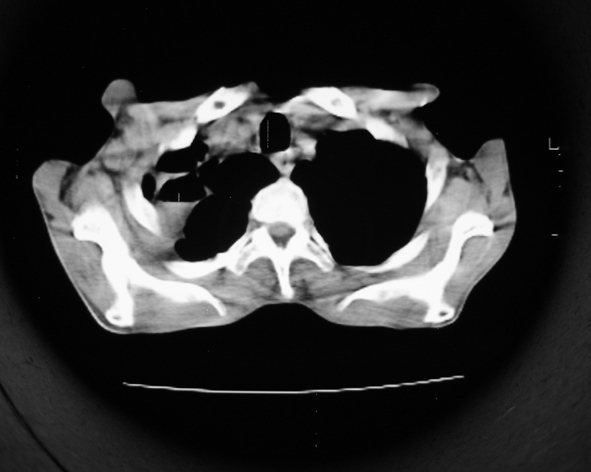

男53岁,咳嗽气短,以往身体健康.

右肺上叶多发多形态空洞及增殖灶,可见团块钙化,胸膜肥厚、粘连,考虑继发型肺结核可能性大

1.右肺上叶干酪性肺炎,2。肺气肿,肺大泡